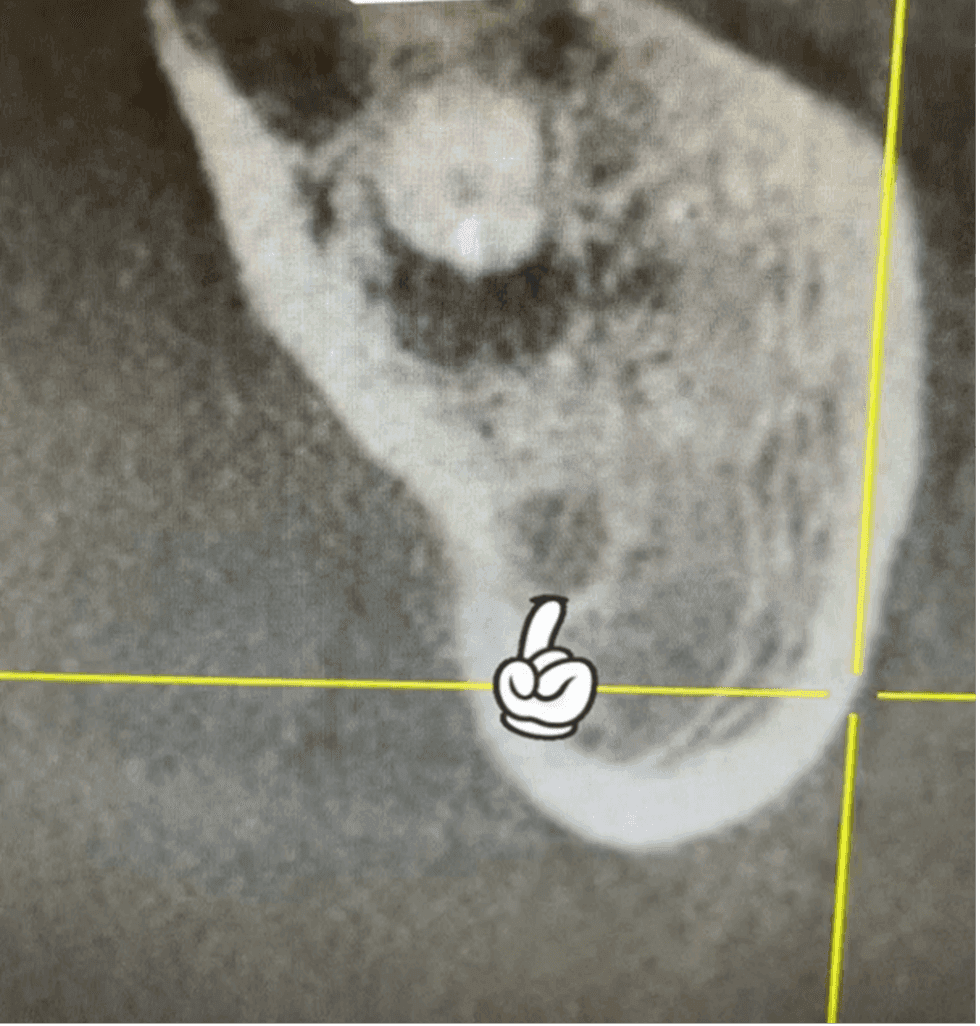

İlk seans kanallara kalsin yerleştirildi ve hastadan alınan tomografi incelendi. Yapılan 3 boyutlu değerlendirmede kök ucundaki lezyonlu alanın kemikle çevrili olduğu, alt kısımdaki mandibular kanalla ilişkisinin olmadığı tespit edildi ve tedaviye cerrahi olmadan ortograd yöntemle devam edilmesi kararı alındı (RESİM 5).

RESİM 5: Mandibular kanal ve taşkın eğenin olduğu bölge